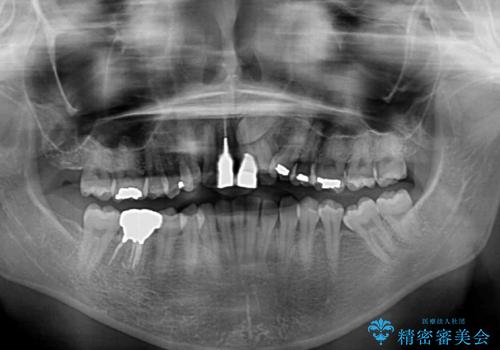

左上の犬歯が埋伏しており、CT画像より萌出は困難と判断されたため、残存している歯にて歯列と咬合を整えることとしました。

前歯のクラウンは、歯肉内深くに削り込まれており、歯肉の炎症が継続していたため、矯正治療後に歯周外科処置を行い、歯肉の腫れを改善させました。